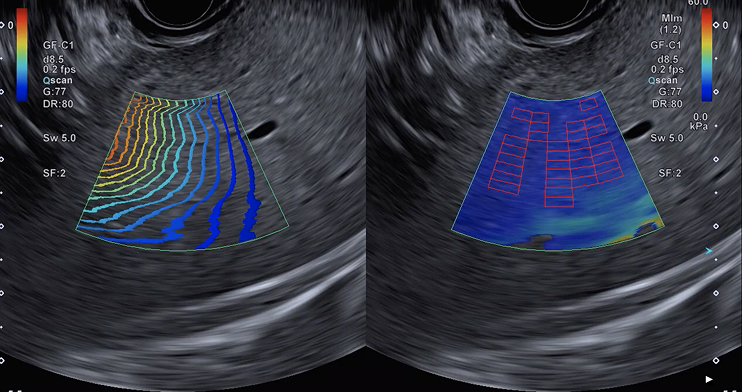

Real-time Tissue Elastography (RTE)

RTE is an additional tool for use in tissue diagnosis. This imaging modality assesses tissue strain in real time and displays the measured differences in tissue stiffness as a color map. The color image shows tissue elasticity, or stiffness in the area of interest, which may help indicate disease processes. This may help the physician identify the appropriate areas for biopsy.11